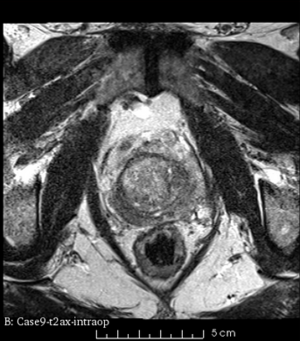

Case 9

Reference intraop volume

Reg Result Slicer 3.6 with ITKv3

Reg Result Slicer 4.4 with ITKv4

We used this sample data with Reader 1 segmentations to visually evaluate differences in the registration results. All three results of BRAINSFit with ITKv3 in Slicer 3.6 look reasonable. Using BRAINSFit with ITKv4 in Slicer 4.4 creates a reasonable result for Case 7, but look strongly distorted towards the edges of the bounding box in Case 8 and 9.